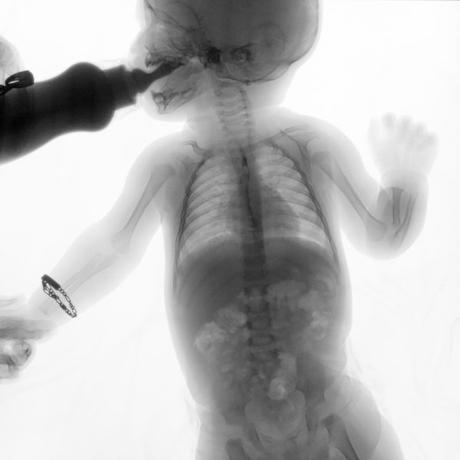

ESTUDIO SOLICITADO: SERIE ESOFAGOGASTRODUODENAL.

Se realiza Esofagograma con material de contraste baritado, por vía oral y por medio de control fluoroscópico se toman distintas proyecciones observando lo siguiente.

Se observa mecánica de la deglución con adecuado paso de medio de contraste de faringe a esófago sin presencia de defectos de llenado depósitos anómalos o fuga del mismo.

ESÓFAGO se observa de situación, calibre y trayecto normal. Contornos regulares y bien definidos. No se observan depósitos anómalos, defectos de llenado o fuga del medio de contraste.

UNION ESOFAGOGASTRICA se observa con calibre y situación normal. Sin observar reflujo a las maniobras de valsalva

ESTOMAGO se observa en su situación habitual, distendido, sin defectos de llenado.

- Actualmente no se demuestra Reflujo gastro-esofágico.

- Estudio de apariencia normal.